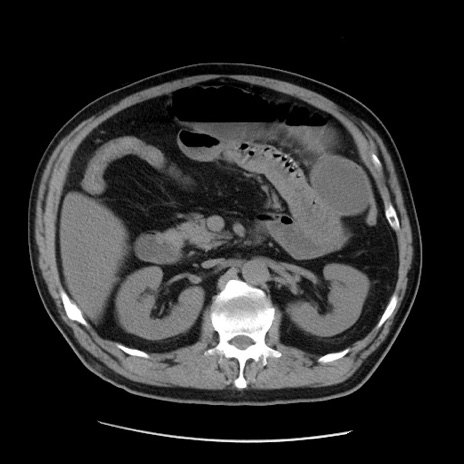

症例20(横断像)

【症例】 60歳代男性

【主訴】 腹部膨満、嘔吐

【現病歴】5日前頃より倦怠感を認め食事量減少し4日前の朝嘔吐、食事摂取困難となった。 3日前近医受診し点滴施行され整腸剤などを処方された。 当日他院を受診し、腹部膨満著明、炎症反応の上昇(CRP10.8、WBC11200)あり、紹介受診となる。

【身体所見】 意識JCS1 受け答えがはっきりしないBP 111/57mHg、 P 67bpm、、BT35.2°C、SpO2 97%(RA)、 腹部:膨隆、打診で鼓音あり、全体的に圧痛有り、腸蠕動音(-)、反跳痛ははっきりせず。

【データ】WBC 11400、CRP 14.20